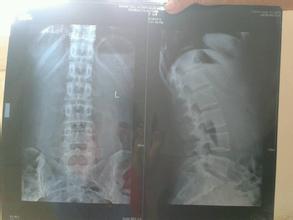

导读: 退化的椎间盘逐渐失去水份,椎间隙变窄,纤维环松弛向周边膨出,椎体不稳,纤维环在椎体边缘外发生撕裂,导致髓核之突出,将后纵韧带的骨膜顶起,其下面产生新骨,形成骨刺或骨质增生。